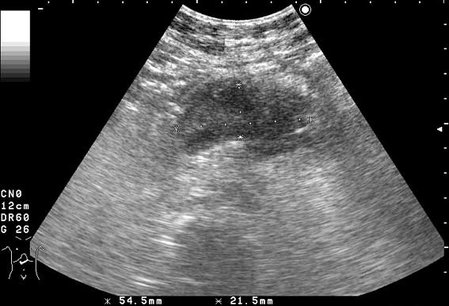

УЗИ панкреас: аденокарцинома тела

Женщина 37 лет поступила в хирургическое отделение с жалобами на боли в животе.

На эхограмме продольный срез п.ж.

Гипоэхогенное образование в области тела, с неровными контурами.Инга писал(а):Можно подробнее- каких именно?KapustinSV писал(а):Больше данных за опухоль панкреас.

Цилиндроклеточная аденокарцинома.